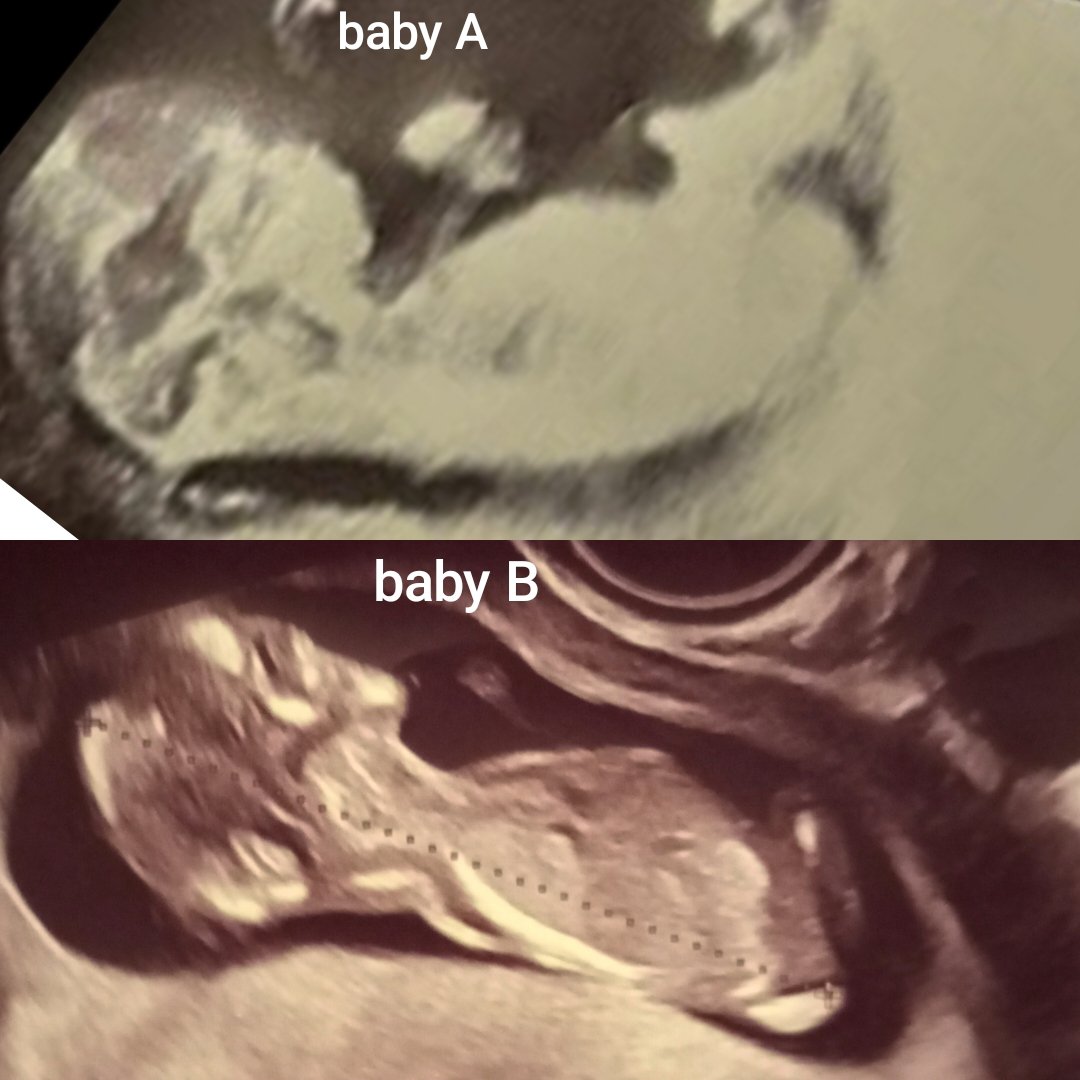

Ahojte, dá sa podla nejakých znakov odhadnúť pohlavie už v 12tt? Dali by ste svoje tipy prosím? 🙏 Baby A už je na svete a jeho pohlavie viem, zaujíma ma, či väčšina uhádne správne. Baby B, je aktuálne v brušku, pohlavie netuším a som strašne nedočkavá..

Na obrázku A nevidím žádný pohlavní hrbolek. Na obrázku B by to mohl lékař poznat, ale neznám žádného, který by to řekl ve 12. týdnu. Odhadovat nebudu, k čemu by to bylo, je brzy, je to 50:50. 😉